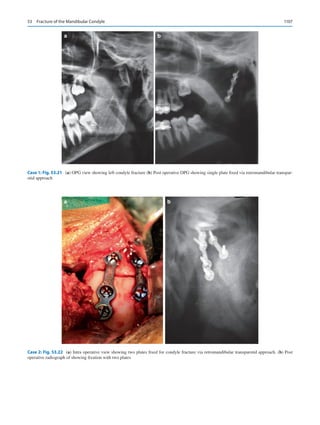

2.	Raju VK.  Suśruta of ancient India. Indian J Ophthalmol.

2003;51:119–22.

3.	Paul G. The future of maxillofacial surgery as a specialty of den-

tistry. J Maxillofac Oral Surg. 2017;16(1):1–2. Published online

2017 Jan 16.

4.	Revised 2007 regulation of the Dental Council of India, Gazette of